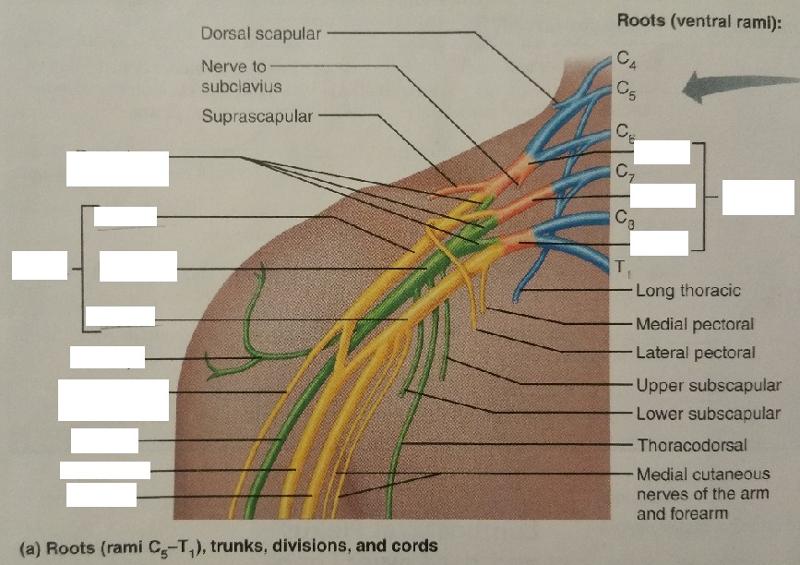

The brachial plexus arises from the ventral rami of what cervical and thoracic nerves?

C5-T1

The brachial plexus after being rearranged consecutively into trunks, divisions, and cords, finally becomes subdivided into what 5 major peripheral nerves?

1. axillary nerve

2. radial nerve

3. median nerve

4. musculocutaneous nerve

5. ulnar nerve

Identify the blanks.

Identify the blanks.